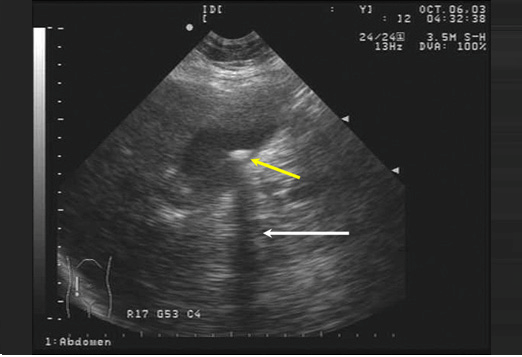

soi_ong_mat_chu

sỏi ống mật chủ